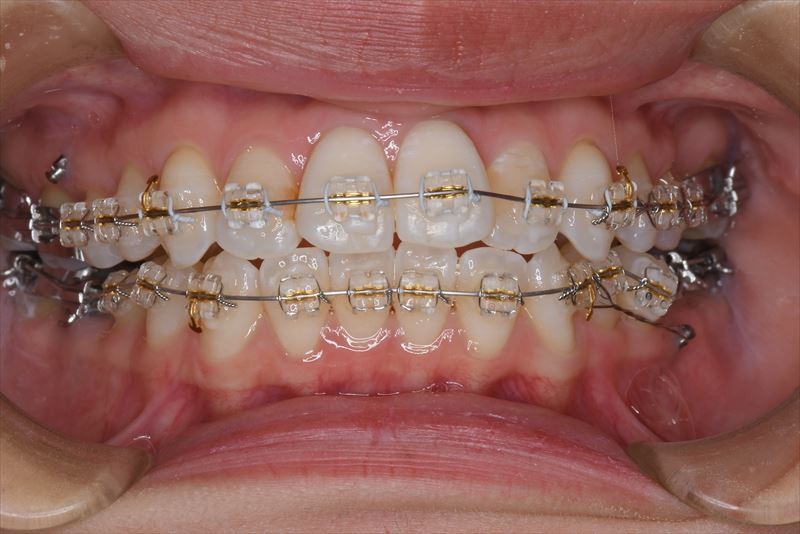

治療中